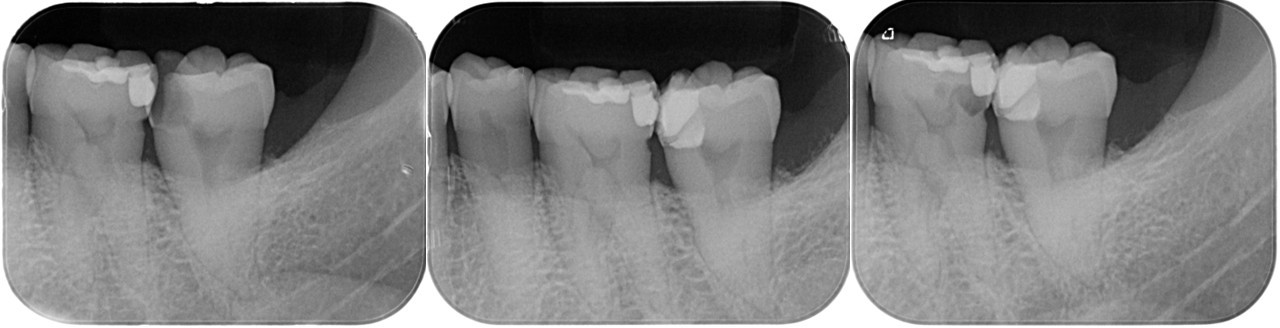

(図14)VPT症例

露髄面の大きさは関係なく正常な歯髄が存在し、健全象牙質上にMTAのセメント層が3ミリ確保できれば良好な結果が得られる

(図15)術後5年経過

髄角付近にデンティンブリッジ形成による硬組織の生成が確認できる

左:2017.07.31 中:2017.07.31 右:2018.10.15